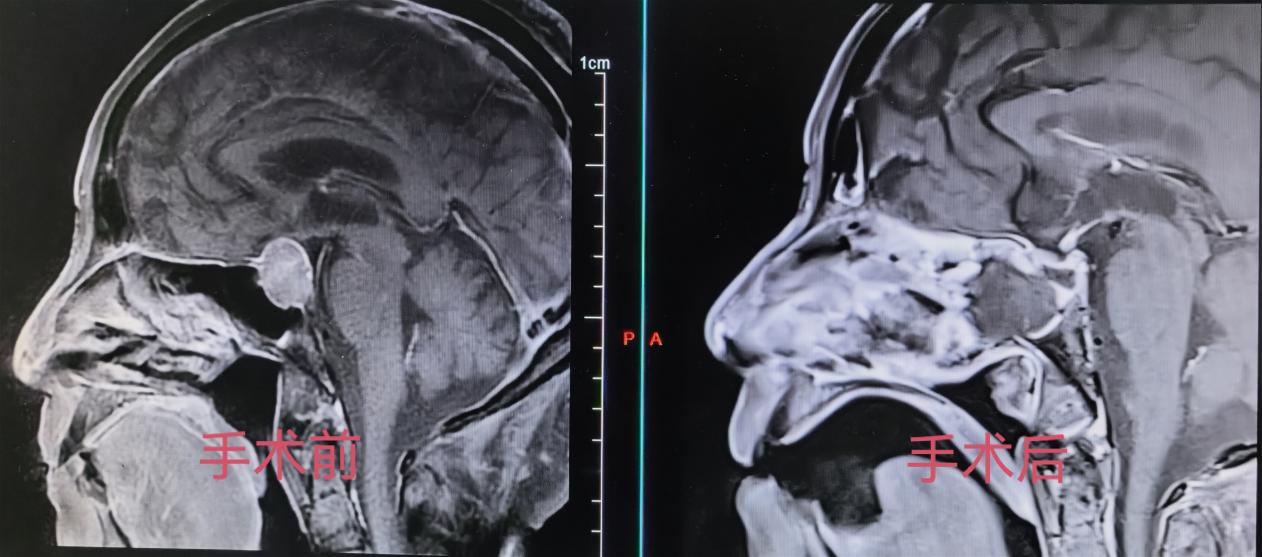

为最大程度降低手术创伤,保障老人安全,神经外科团队决定采用目前先进的“双镜联合”微创技术——即在神经导航精准定位下,结合显微镜的放大照明与神经内镜的广角、抵近观察优势,实施肿瘤切除。该术式无需开颅,通过鼻腔自然通道,即可在狭小的颅底空间内精细操作,具有损伤小、出血少、恢复快的特点,适合身体虚弱的高龄患者。

手术由经验丰富的李东海主任医师、肖利民副主任医师及其团队完成,麻醉科全程严密监护。术中,团队密切配合,凭借娴熟的技术,清晰地辨识并保护了垂体柄、颈内动脉、视神经等重要结构,最终将肿瘤完整切除。手术历时约两小时,过程顺利,出血量极少。